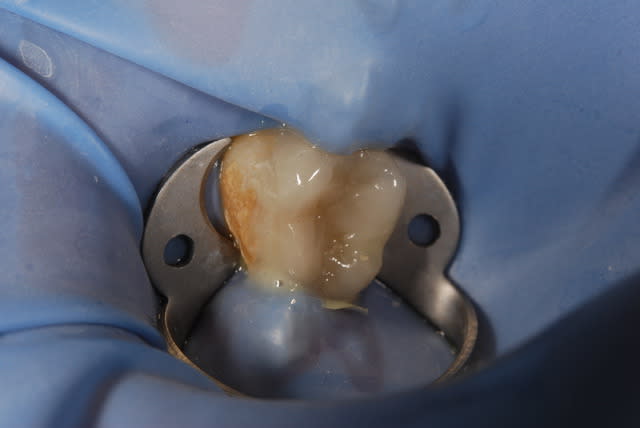

Oui .(photos 2 et 3 d'hier)